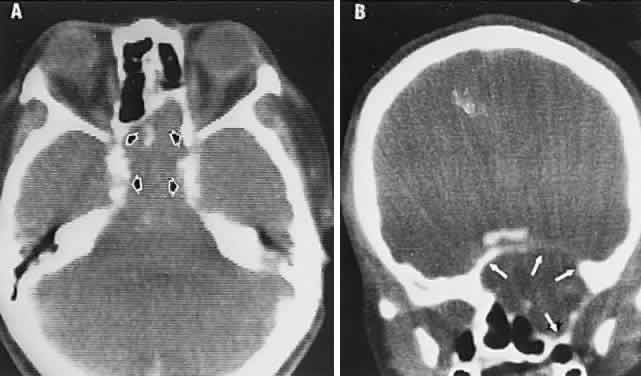

The retinal variety may be admixed in a person who suffers the more conventional attacks of migraine. It is presumed that vasospasm in the retinal circulation determines transient hypoxia, perhaps somewhat similar to the visual cortical event. On rare occasions, the fundus has been examined during typical retinal migraine episodes, and arterial constriction has been described. Wolter and Burchfield106 photographically documented such an episode and demonstrated mild “retinal edema”; vessel narrowing is also evident (Fig. 8). Fortunately, permanent complications of retinal migraine are rare. These may take the form of central retinal artery occlusion or ischemic papillopathy (see Volume 2, Chapter 16); nerve fiber bundle visual field defects may be demonstrated (Fig. 9).

Fig. 8. Retinal migraine. A. During amaurotic episode. Note the dusky appearance of the fundus, increased retinal sheen (possibly edema), and dark narrowed veins (arrows). The disc is also hyperemic. B. Fundus after episode. Compare paired arrows. (Courtesy of Dr. J. Reimer Wolter)